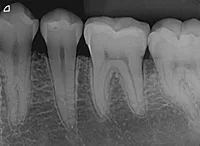

Qual método é apresentado na imagem?

Método de Parma

Incidências Cruzadas

Método de Le Master